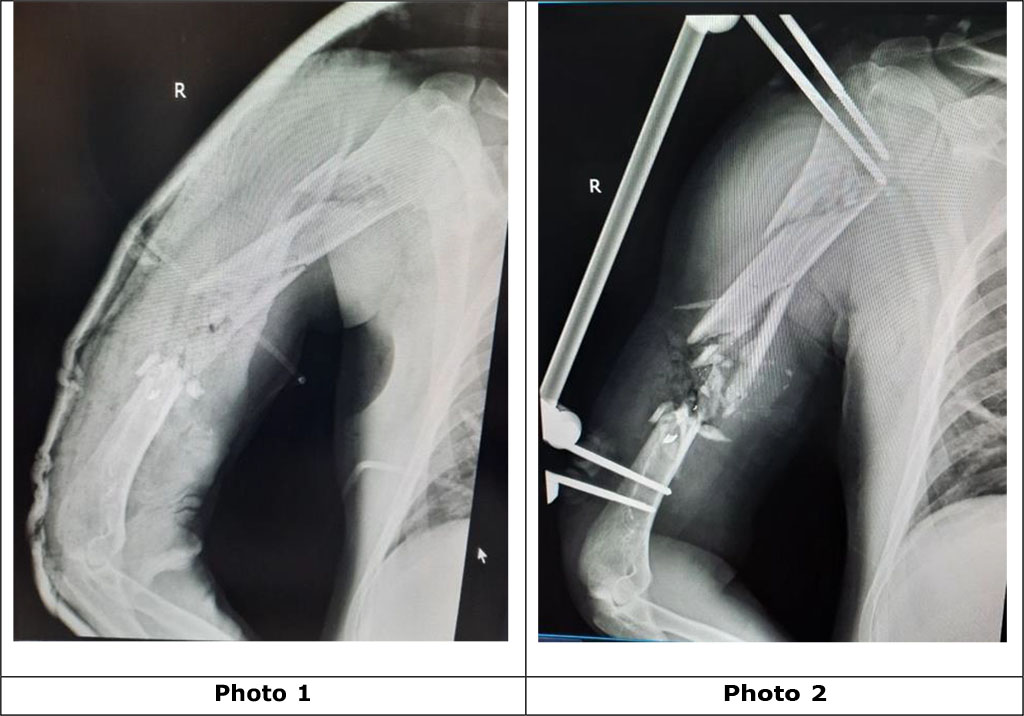

Wounded man, 38 years old. He was wounded during military operations on the territory of Ukraine. He was admitted for treatment with a diagnosis: blind gunshot wound (April 25, 2022) of the upper third of the right shoulder with a gunshot fracture along the upper and middle third of the right humerus with displacement of fragments, the formation of a bone defect along 6 cm of the diaphysis of the right humerus and the presence of extraneous bodies (metal fragments) in the fracture projection (photo 1). Primary surgical treatment of the gunshot wound, external fixation of the fragments of the right humerus with a rod apparatus of external fixation was performed as a priority (photo 2).

Photo

1. Radiographs of the right shoulder with a gunshot multifragmentary

fracture along the middle and upper third of the diaphysis of the

humerus with displacement of the fragments, a defect in the bone

structure, and foreign bodies (metal fragments) before the operation

2. Photo-radiogram after the operation of the primary surgical

treatment of the gunshot wound, external fixation of the fragments of

the right humerus with a rod apparatus of external fixation.